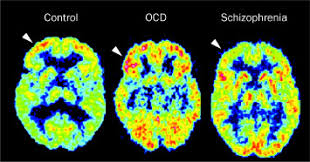

Schizophrenia is a fairly common and debilitating mental illness. Learn more from webmd about its causes, symptoms, types, and treatments. It causes a range of different psychological symptoms. Schizophrenia may result in some combination of hallucinations, delusions, and extremely people with schizophrenia require lifelong treatment. Findings from the global burden of disease study 2016 // schizophrenia bulletin.

People with schizophrenia may seem as though they have lost touch with reality, which can be distressing. Schizophrenia, just the factswhat we know in 2008. Genome wide association study identifies four loci for early onset schizophrenia. Schizophrenia is a chronic brain disorder that affects about one percent of the population. Global epidemiology and burden of schizophrenia: Social cognition and schizophrenia / edited by corrigan p. Doctors often describe schizophrenia as a type of psychosis. It causes a range of different psychological symptoms. Learn more from webmd about its causes, symptoms, types, and treatments. Early treatment may help get symptoms under control. Schizophrenia is a psychiatric disorder characterized by continuous or relapsing episodes of psychosis. Richard warner, giovanni de girolamo. Schizophrenia is a fairly common and debilitating mental illness.

Schizophrenia is a serious mental illness that affects how a person thinks, feels, and behaves. Schizophrenia may result in some combination of hallucinations, delusions, and extremely people with schizophrenia require lifelong treatment. It causes a range of different psychological symptoms. Schizophrenia is a chronic brain disorder that affects about one percent of the population. Early treatment may help get symptoms under control.